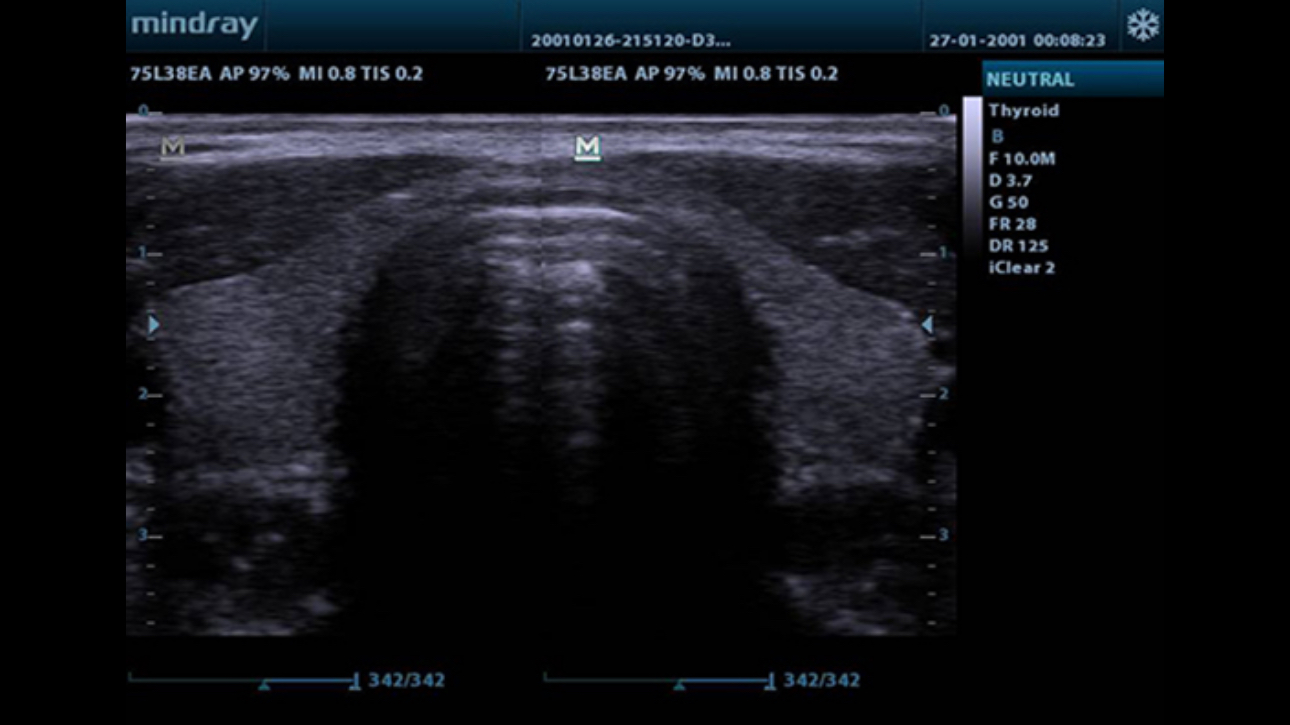

Tissue Harmonic Imaging

Utilizing second harmonics generated from tissue boundary layers, THI significantly enhances contrast resolution and improves image quality especially for technically difficult subjects.

TSI

Tissue Specific Imaging optimizes the image quality based on the properties of the tissue being scanned. Four imaging options are available including general, muscle, fluid and fat.

iClear?

Gain improved image quality based on auto structure detection.